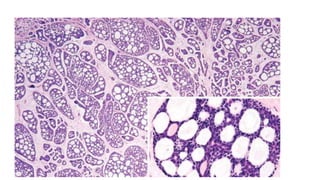

Cribriform pattern

• Punched-out or “swiss cheese” arrangement of tumor cells are seen

surrounding acellular spaces containing mucoid/ hyaline material.

• Tumor cells – dense basophilic nuclei with inconspicuous nucleoli.

Cribriform pattern • Punched-outor “swiss cheese” arrangement of tumor cells are seen surrounding acellular spaces containing mucoid/ hyaline material. • Tumor cells – dense basophilic nuclei with inconspicuous nucleoli.